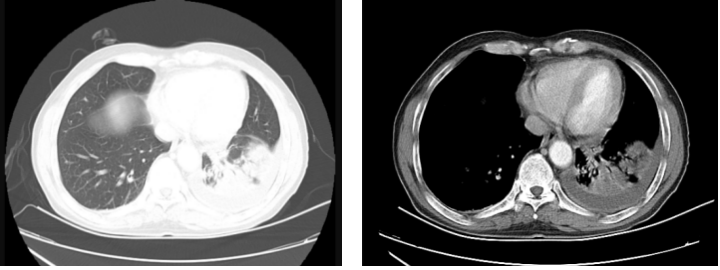

2024年3月31日胸部CT:左肺下叶肿块,肿瘤性病变可能,伴远端阻塞性肺炎;双肺小结节,转移待排;左肺门一枚淋巴结肿大,转移可能;左侧胸腔积液。

经上述治疗后,患者2024年4月至2025年2月规律复查胸部CT可见,左肺下叶肿块影呈缩小趋势,疾病稳定。

2025年3月2日患者胸部平扫CT示,左肺下叶近肺门处软组织密度肿块影,考虑肿瘤及治疗后改变伴阻塞性炎症,肿瘤较前(2024年11月21日)肿瘤增大;双肺散在多发结节,较前增多、部分增大,考虑为转移可能;左侧胸膜结节状增厚,建议进一步增强检查除外胸膜转移。

经上述治疗后,2025年5月12日患者复查胸部CT平扫示,左肺下叶近肺门处软组织密度肿块影,考虑肿瘤及治疗后改变伴阻塞性炎症,肿瘤较前(2025年2月26日)稍减小;双肺散在多发微、小结节,较前部分减小、部分空洞形成,考虑为转移瘤及治疗后改变可能。左侧胸膜结节状增厚,较前大致相仿,胸膜转移待排。